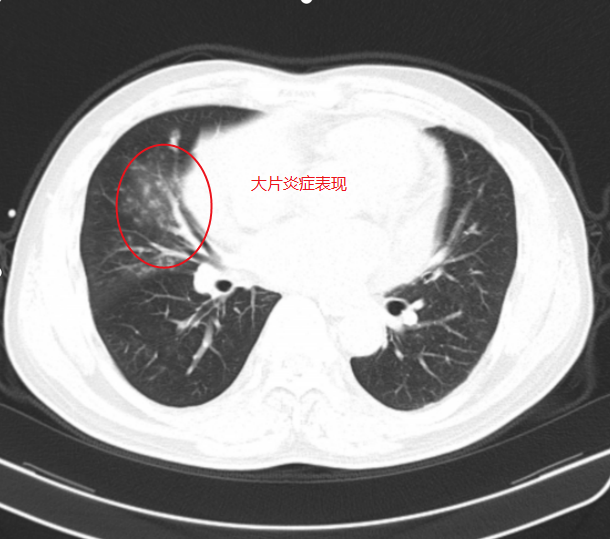

▲入院CT见右下肺多发炎症,未见明显支气管扩张征象

该患者因“咯血2天”入院,入院后医护人员迅速开展全面检查。胃镜检查未发现胃溃疡出血迹象,CT检查也未显示支气管扩张,但患者持续大量咯血,即便使用垂体后叶素等止血药物,病情仍未得到有效控制,甚至无法平卧,随时面临呼吸道堵塞、窒息的生命危险。面对这一危急情况,肿瘤科二区和麻醉科专家紧急会诊,综合评估后决定为患者实施经口支气管插管全麻下支气管动脉造影+栓塞术治疗。